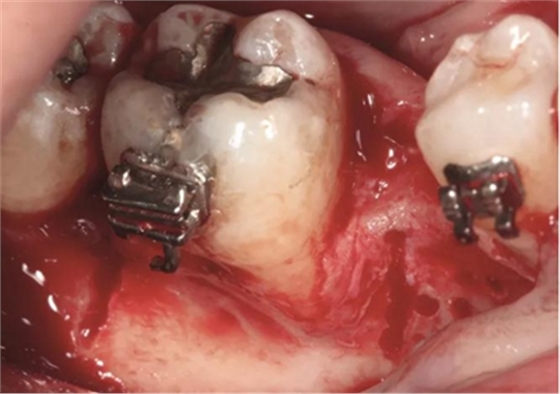

圖5e. 去皮質(zhì)后,同種異體凍干骨顆粒放置于受植區(qū)

圖5f. 膠原膜覆蓋并適應(yīng)于受植區(qū)